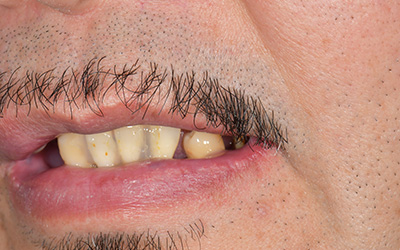

【歯周病で多数歯欠損③】【職業:俳優】芸能人は歯が命 膿が出て歯がぐらつくことで食事が怖くコンプレックスだった口元から自信をもって笑える長所へ

患者さま情報:40代 男性

治療期間:1年

治療費:4,082,100円(税込)

リスク:歯茎がない場合、移植を行う場合があります。

副作用:術後の痛みは投薬で抑えられたが、腫れは見られた

before

after